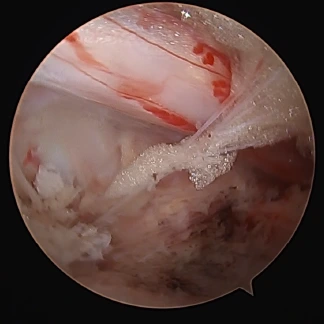

当院では、膝関節、肩関節(腱板修復術、バンカート修復術)、手指(手根管開放術)、股関節の疾患に対して「関節鏡視下手術」を行っています。関節鏡視下手術とは、まず手術をする関節の周囲に6~7mmの皮膚切開を数個作り、この小さな切開口から細いカメラ(内視鏡)や手術器具を関節内に入れて、モニターで内部を目視しながら行う手術のことです。関節鏡を用いる手術では、手術時の切開口が小さくて済むので、術後の回復が早いのが特徴です。体力的にも美容的観点からも患者さんの負担が小さいなどのメリットもあります。

前十字靱帯の損傷はスポーツ時の外傷(ケガ)によるものが多く、そのまま放置していると、半月板や軟骨などの正常な組織が傷つく場合があります。当院では、関節鏡視下手術としては比較的難度の高い「膝前十字靱帯再建術」(ACL)、「膝後十字靱帯再建術」(PCL)の豊富な症例実績を有しています。

腰椎椎間板ヘルニアの術中画像